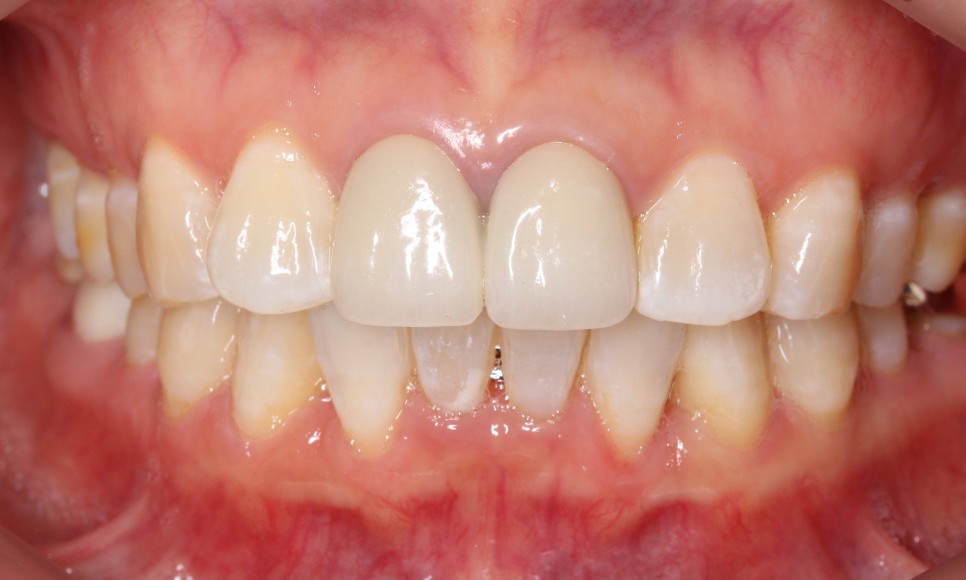

위 사진을 보시면

환자분의 아랫니 상태가

심하게 삐뚤거리는 모습을

확인할 수 있습니다.

치아 사이의 공간이 좁아서

작은앞니의 각도가

심하게 회전된 모습인데요.

반면, 윗니는 아랫니에 비해

비교적 가지런한 상태였는데요.

이렇게 윗니는 고른 편인데

아랫니만 삐뚤어짐이 심한 상태일 땐

교정 정밀진단을 통해

아랫니만 2D교정 (설측 부분교정)으로

개선이 가능합니다.